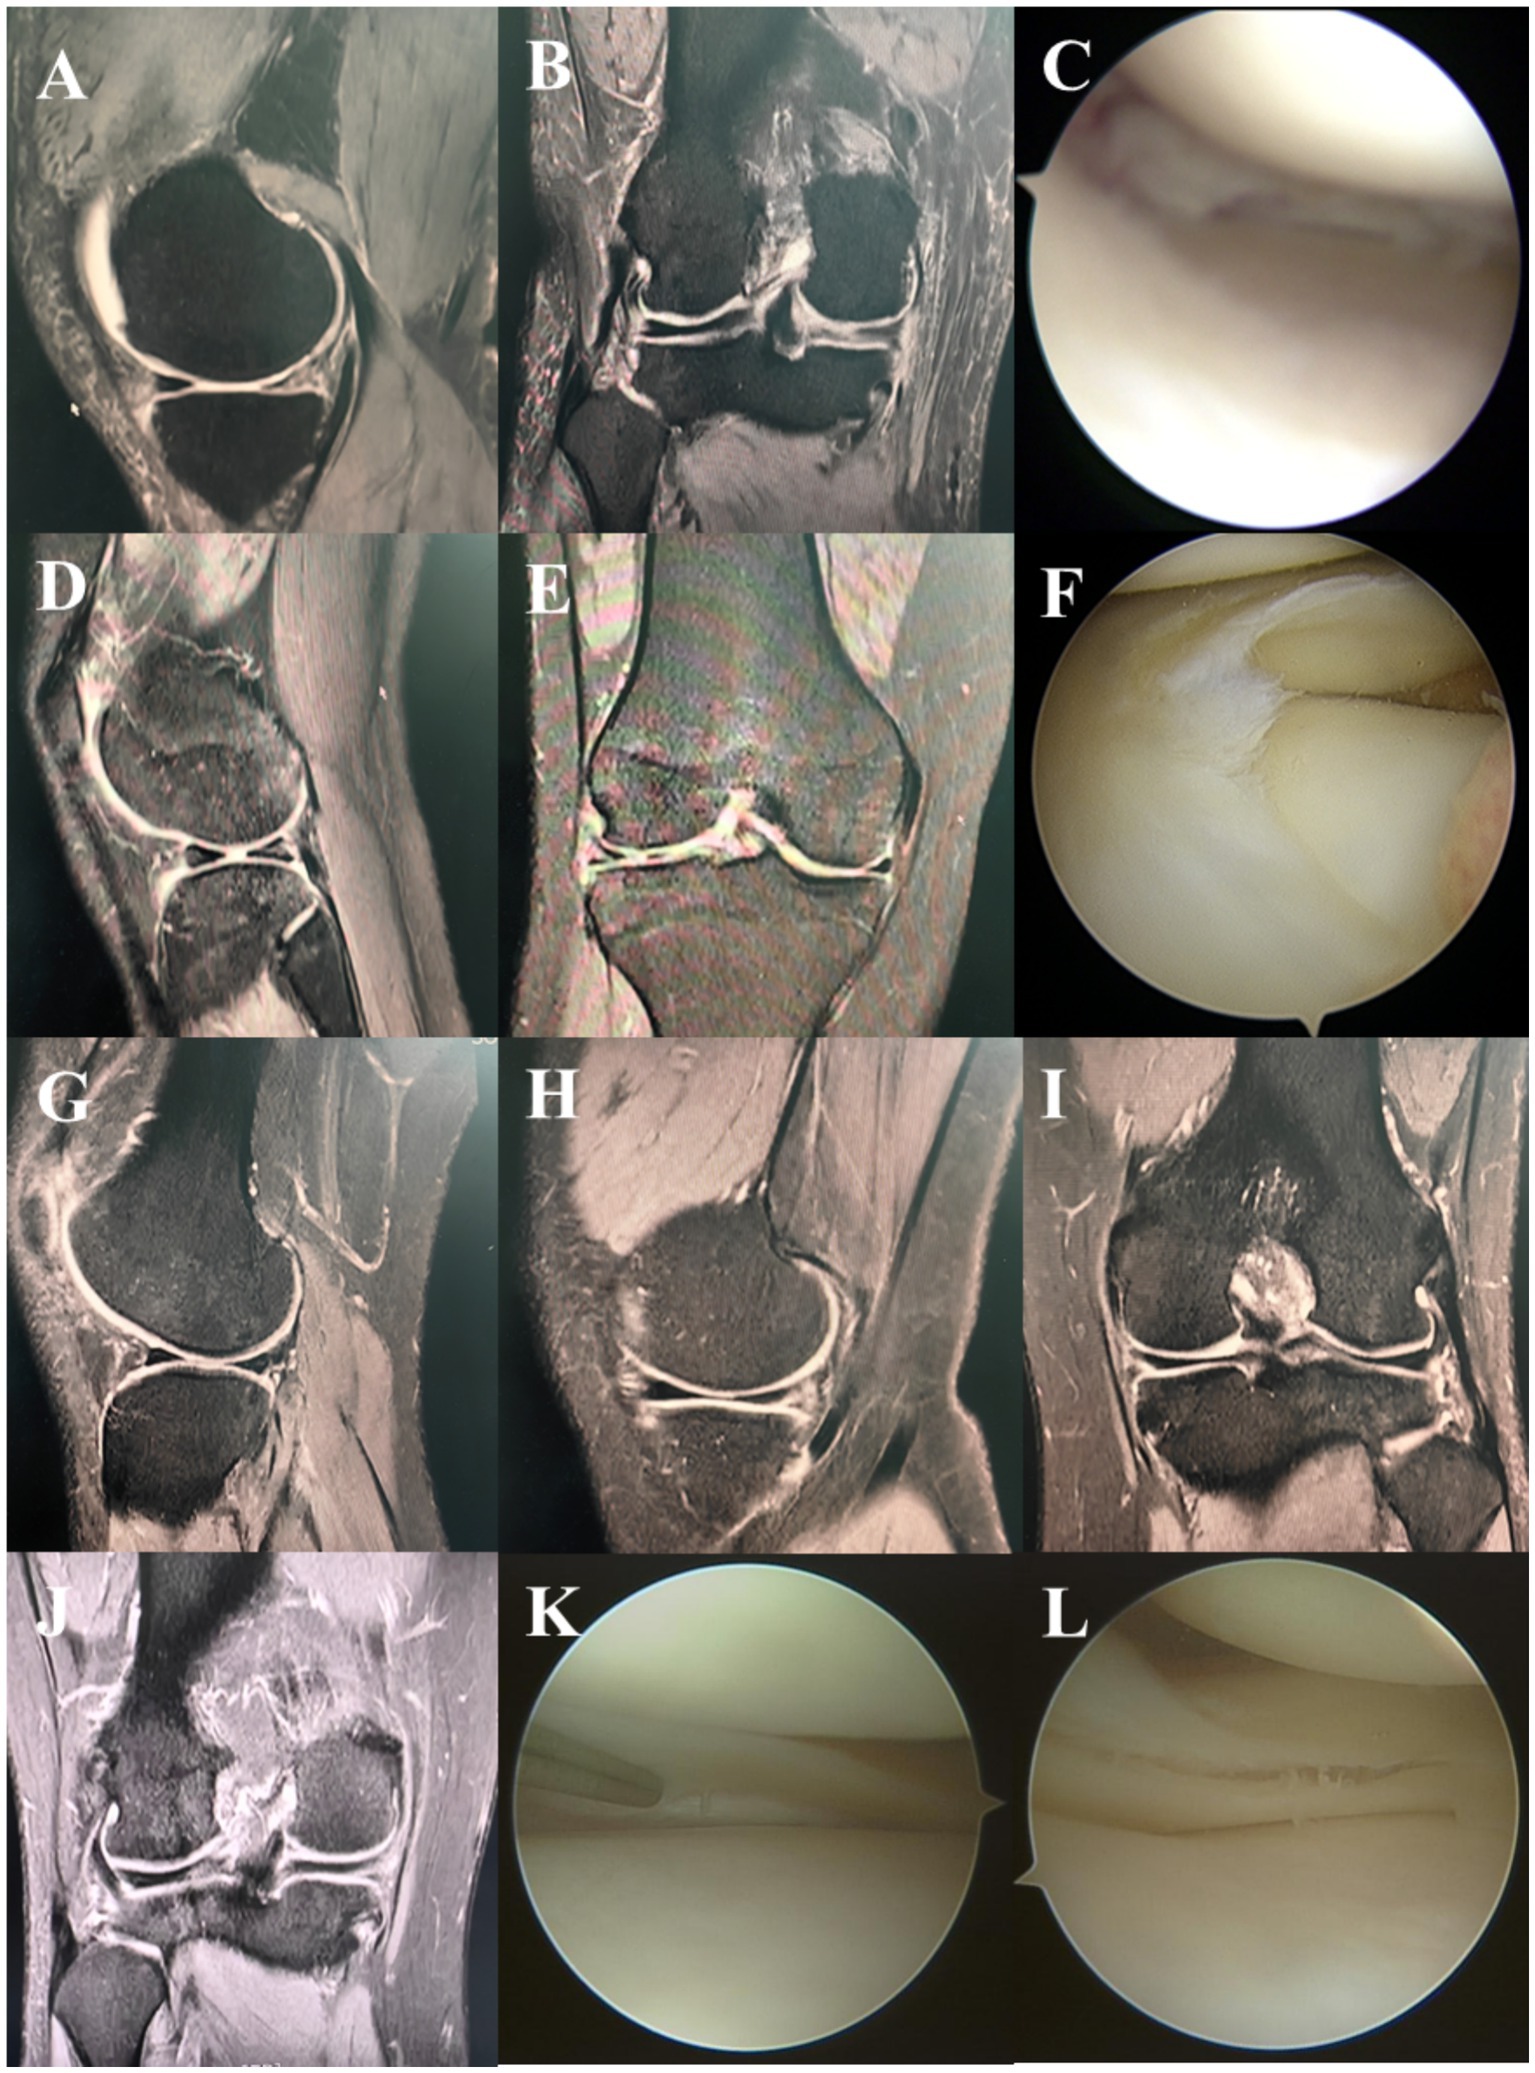

A total of 37 patients were included in the study, with an average age of 39.24 ± 14.06 years, comprising 18 males and 19 females. Among these patients, 18 presented with right knee injuries, while 19 had left knee injuries, with an average disease duration of 20.54 ± 28.59 months (Table 1). All patients were diagnosed with meniscus injuries through MRI and confirmed via intraoperative arthroscopy (Table 1 and Figure 1).

Figure 1

MRI and arthroscopic images of knees labeled A to L. Images A, B, D, E, G, H, I, and J depict various angles and conditions of knee joints, showing meniscal tears and cartilage conditions. Images C, F, K, and L are arthroscopic views inside the knee, illustrating the surface and internal conditions of the meniscus and cartilage.

Figure 1. Typical cases. MRI sagittal (A), coronal (B) and arthroscopic (C) manifestations of lateral meniscus injury. MRI sagittal (D), coronal (E) and arthroscopic (F) manifestations of medial meniscus injury. MRI sagittal (G,H), coronal (I,J) and arthroscopic (K,L) manifestations of both lateral and medial meniscus injuries.